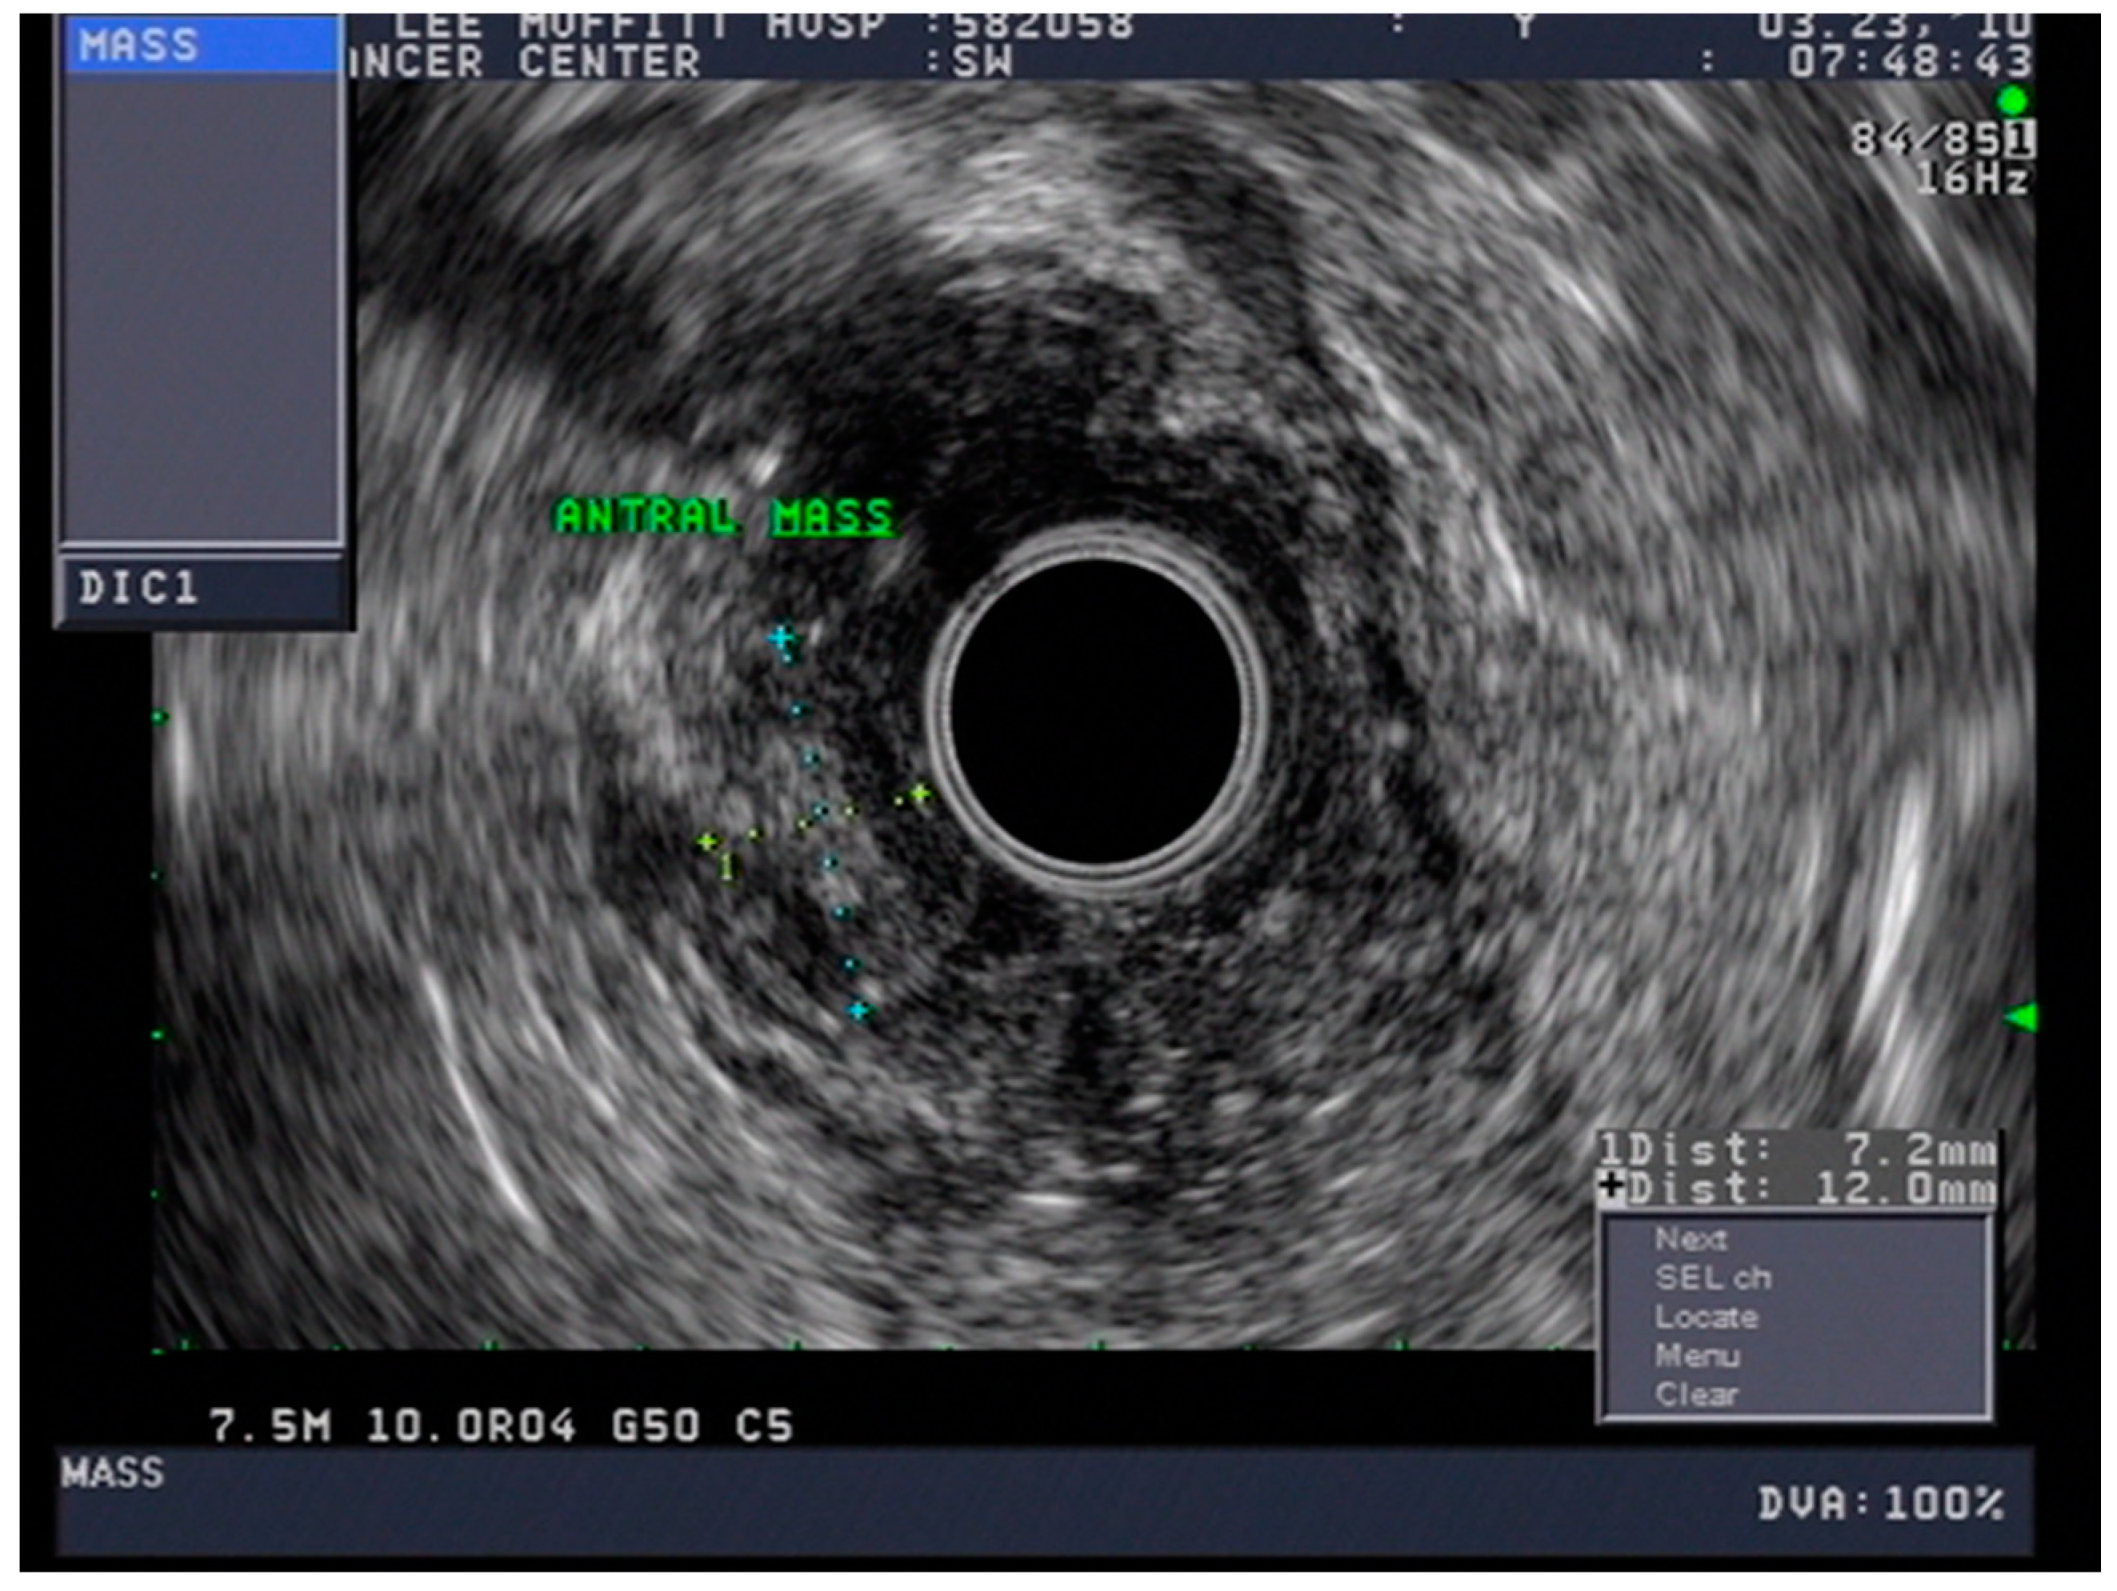

4.3. Endoscopic Ultrasound in Staging of Gastric Cancer